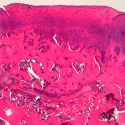

El resultado de esta combinación es la producción de un material que se coloca en el lugar dañado. Según estudios preliminares en conejos, se ha demostrado que, al cabo de tres meses, el organismo ha sido capaz de desplazar el material colocado anteriormente y lo ha sustituido por tejido con aspecto histológico del tejido natural y con una superficie articular totalmente funcional.